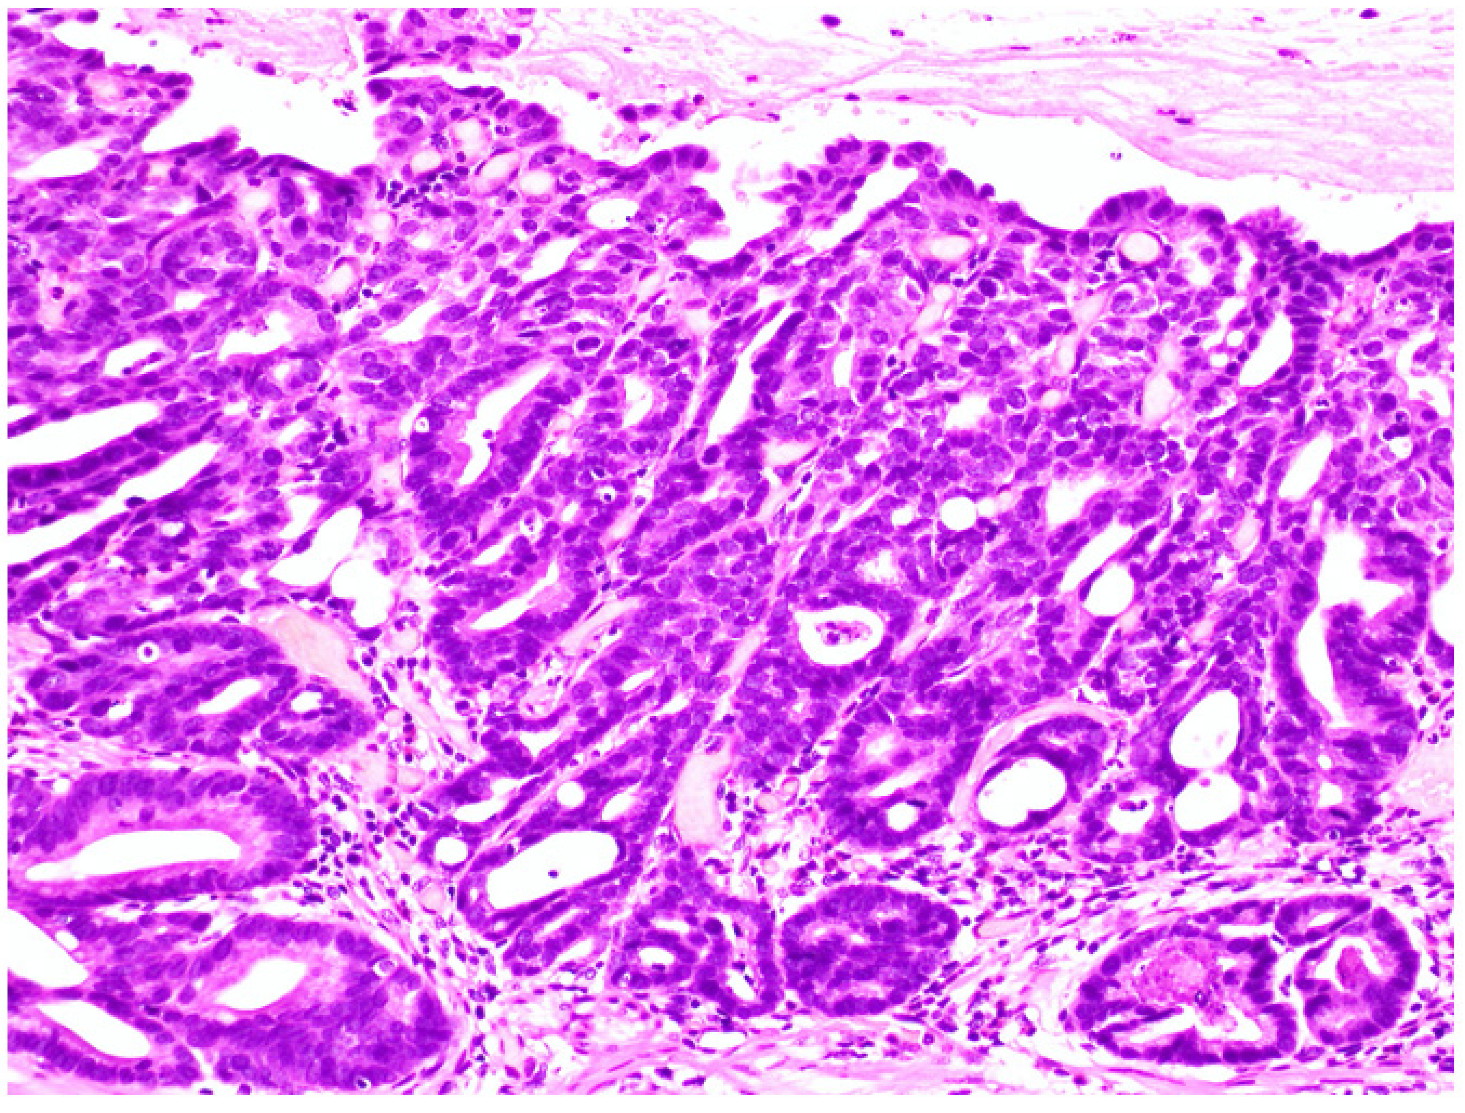

Figure 2.

High-grade dysplasia. Glands have a variable size and shape. The nuclei are irregular in shape and size.